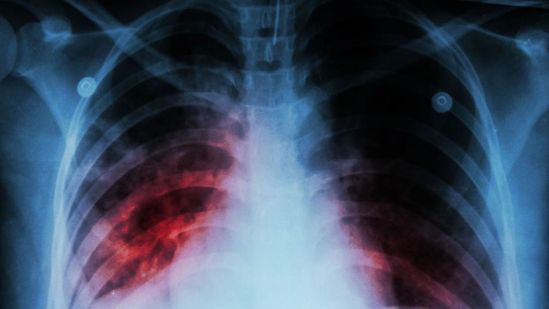

En el marco de la Semana Mundial de la Fibrosis Pulmonar Idiopática, que se conmemora del 16 al 22 de septiembre, la especialista comentó que las enfermedades pulmonares intersticiales son un extenso grupo de trastornos que causan inflamación o cicatrización del intersticio; es decir, el tejido que recubre los pequeños sacos de aire (alvéolos) que le dan la apariencia esponjosa al pulmón, los cuales se expanden en cada respiración permitiendo el intercambio de oxígeno.

Explicó que la Fibrosis Pulmonar Idiopática es una enfermedad enigmática y de difícil manejo, lo que supone un reto para el médico neumólogo porque tiene un pronóstico incierto. “Se caracteriza por un proceso anormal y desconocido de cicatrización del tejido del pulmón que hace que se vuelva rígido y vaya reduciendo su tamaño. A medida que avanza la cicatrización del tejido pulmonar, el paso del oxígeno al torrente sanguíneo a través de los pulmones se hace cada vez más complicado[7]”.

Así, el paciente puede experimentar síntomas como falta de aire, tos persistente, opresión y dolor en el pecho, fatiga, pérdida de peso y acropaquia (deformación de la punta de los dedos de manos y pies en forma de palillos de tambor)[8],[9]. “Dado que la progresión de la enfermedad es variable, con el paso del tiempo la función pulmonar se deteriora de forma gradual e irreversible empeorando la frecuencia e intensidad de los síntomas. Estos episodios se conocen como exacerbaciones y son el principal motivo de urgencias médicas, hospitalización, depresión, ansiedad y muerte”.

Por eso, ante cualquier sospecha es importante que los afectados acudan con un médico neumólogo, quien a través de una serie de estudios podrá determinar su presencia. “Si bien el diagnóstico es complicado, más del 80% de los pacientes con FPI tienen un sonido distintivo tipo velcro (crepitación) que puede detectarse por medio de un estetoscopio[10]. Y, una vez detectada, se debe iniciar tratamiento inmediato”, agregó.